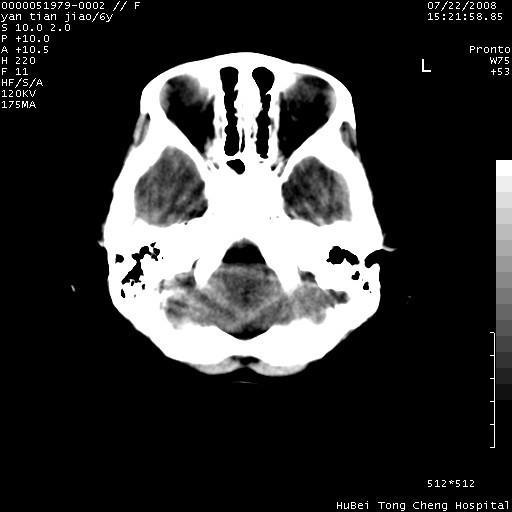

患儿 女,6岁。发热三天,昏迷五小时伴抽搐一次入院。pe:神志不清,浅昏迷状,双侧瞳孔不等大(右侧瞳孔直径3.5mm,左侧瞳孔2.0mm),对光反射迟钝,项强约一指,脑膜刺激征及病理反射阳性;双肺可及痰鸣音;四肢肌张力不高。

临床诊断:病毒性脑膜脑炎并脑疝?

颅脑ct轴位平扫,如下图:

大面积低密度区,可疑脑炎,建议强化!

结合临床症状,符合右颞顶枕叶病毒性脑膜脑炎.建议增强或mri。

右侧低密度区结合临床考虑脑炎